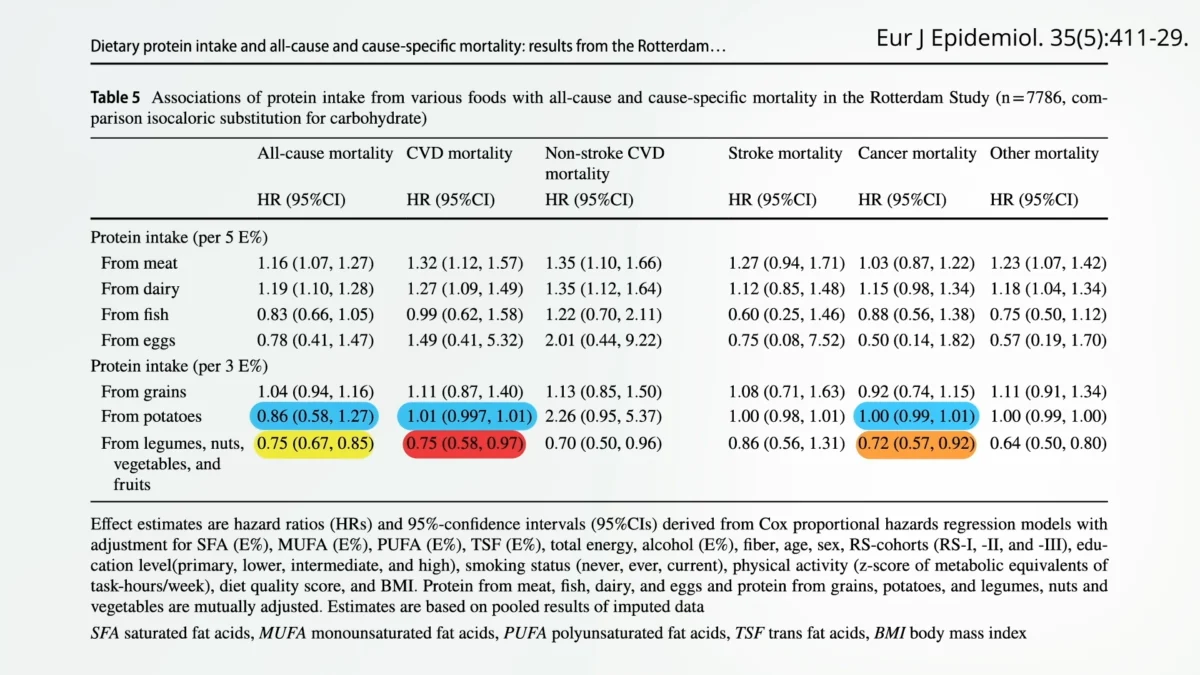

Beyond the Statin Debate: A Strategic Framework for Precision Lipid-Lowering Therapy and Cardiovascular Risk Management

The clinical landscape of cardiovascular preventative medicine is currently undergoing a paradigm shift, moving away from the binary question of whether to initiate statin therapy and toward a sophisticated, individualized…

Billion-Dollar Drugs Recalled for Carcinogen Levels Far Exceeding Those Found in Grilled Chicken Beyond the Statin Debate: A Strategic Framework for Precision Lipid-Lowering Therapy and Cardiovascular Risk Management

Beyond the Statin Debate: A Strategic Framework for Precision Lipid-Lowering Therapy and Cardiovascular Risk Management The Evolving Landscape of Sleep Apnea Treatment: Understanding GLP-1s, Insurance Coverage, and Patient Options